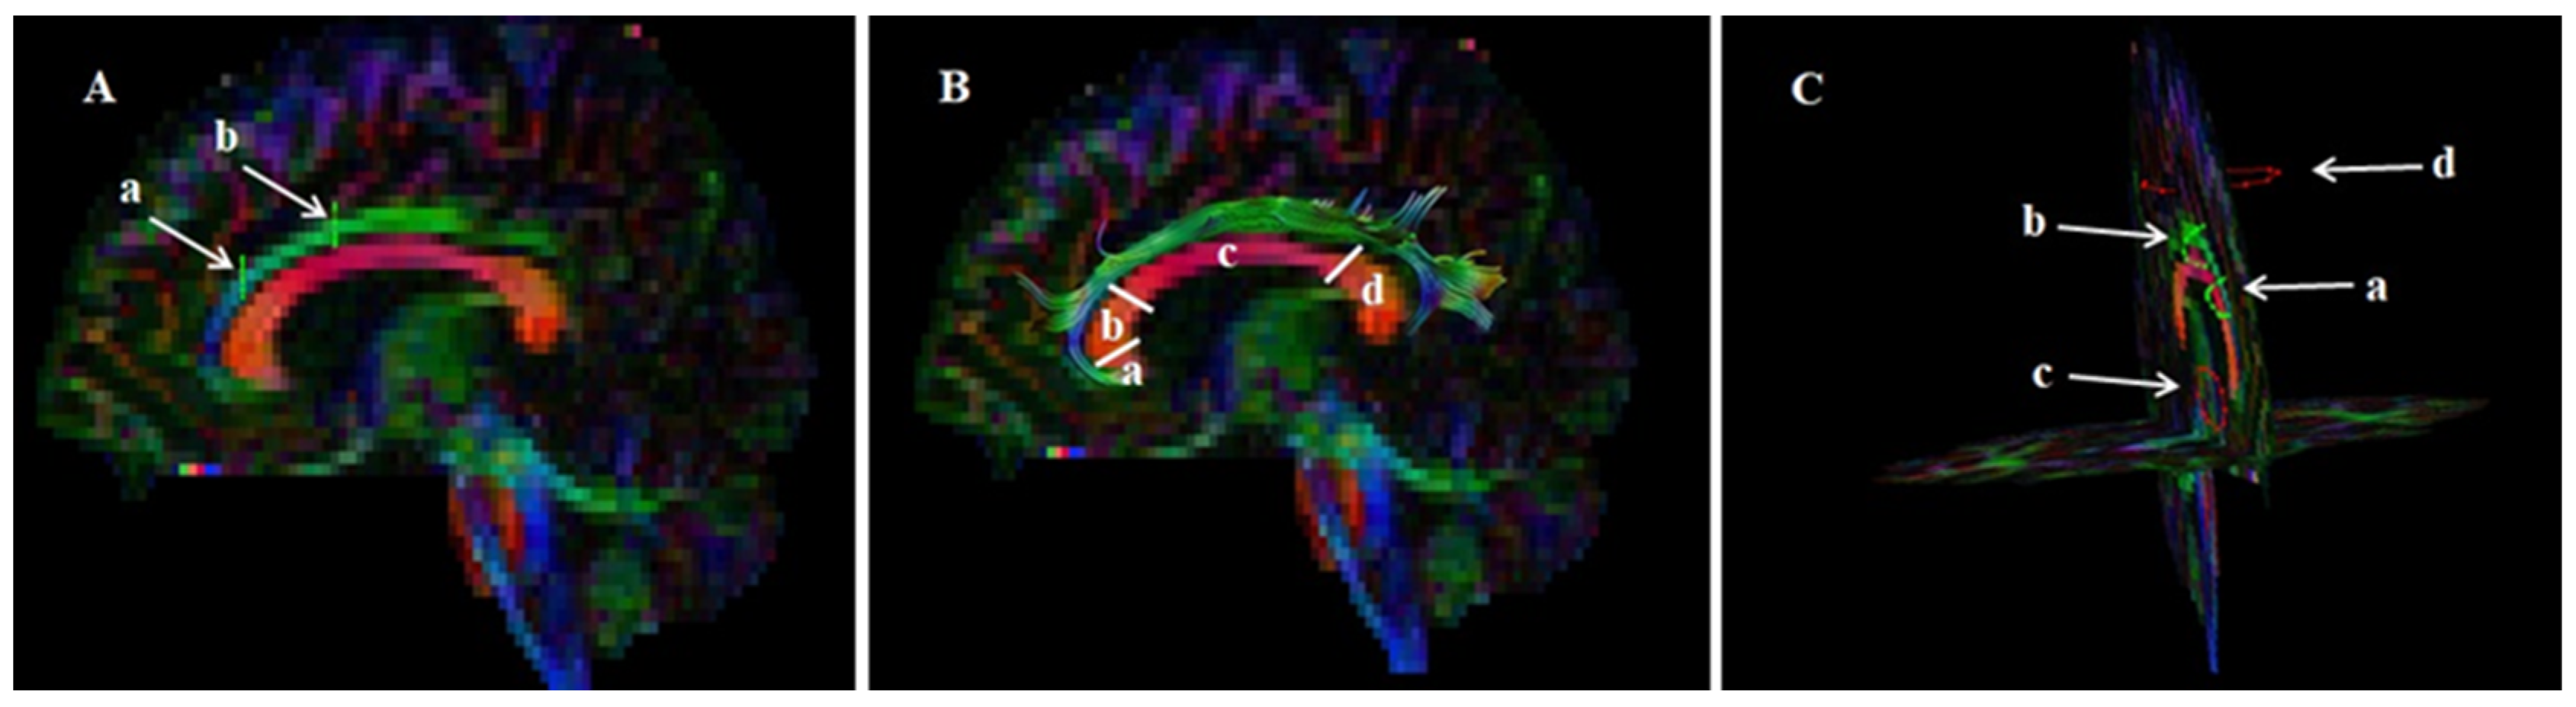

2.2. Acquisition of DTI Data and Image Processing